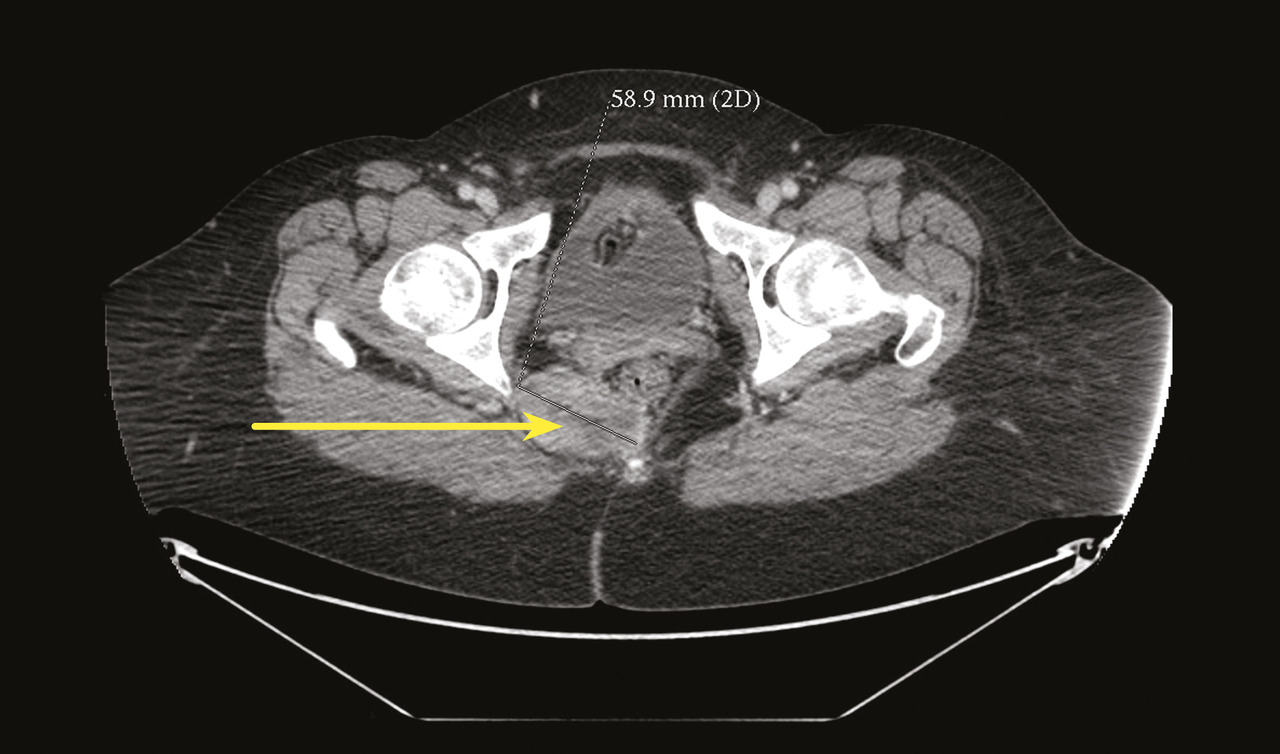

Certains phénomènes compressifs peuvent être à l’origine de NP, comme les contractures myofasciales des muscles de voisinage (muscle obturateur interne ou muscle piriforme) et certains processus tumoraux, qui bien qu’exceptionnels, doivent toujours être recherchés, imposant la réalisation d’une imagerie par résonance magnétique (IRM) ou d’un scanner pelvien (fig. 4).

Devant ce type de syndrome douloureux, une exploration pelvi-périnéale, idéalement une IRM, recherche une anomalie anatomique ou tumorale.